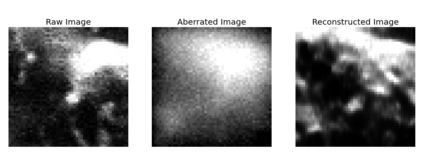

The quality of microscopy images often suffers from optical aberrations. These aberrations and their associated point spread functions have to be quantitatively estimated to restore aberrated images. The recent state-of-the-art method PhaseNet, based on a convolutional neural network, can quantify aberrations accurately but is limited to images of point light sources, e.g. fluorescent beads. In this research, we describe an extension of PhaseNet enabling its use on 3D images of biological samples. To this end, our method incorporates object-specific information into the simulated images used for training the network. Further, we add a Python-based restoration of images via Richardson-Lucy deconvolution. We demonstrate that the deconvolution with the predicted PSF can not only remove the simulated aberrations but also improve the quality of the real raw microscopic images with unknown residual PSF. We provide code for fast and convenient prediction and correction of aberrations.